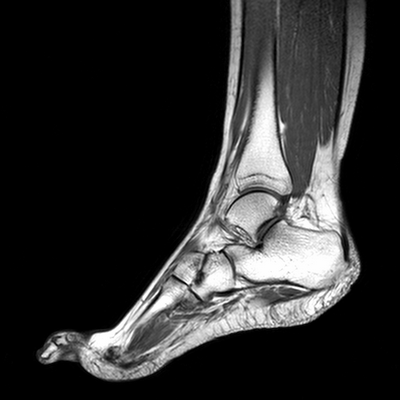

МРТ голеностопного сустава в сагиттальной плоскости. Отмечается полный разрыв пяточного сухожилия с признаками повреждения паратенона, реактивного паратендинита.